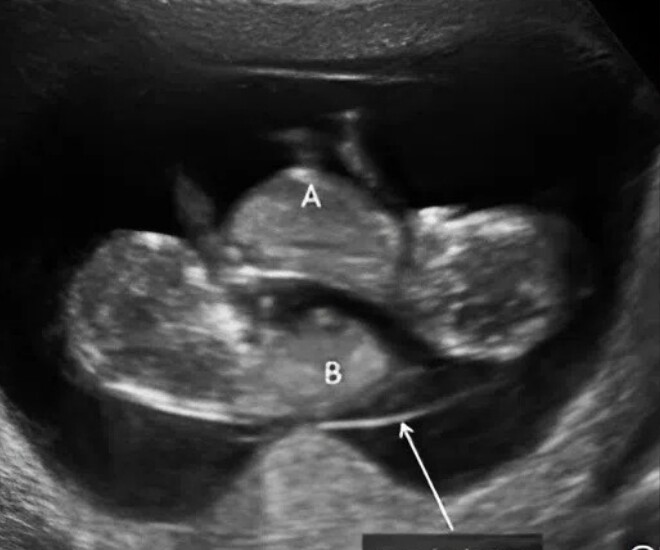

Khi vào viện siêu âm, bác sĩ bất ngờ thông báo, cô không hề mang thai đơn như những lần siêu âm trước, mà là một ca đa thai đặc biệt.